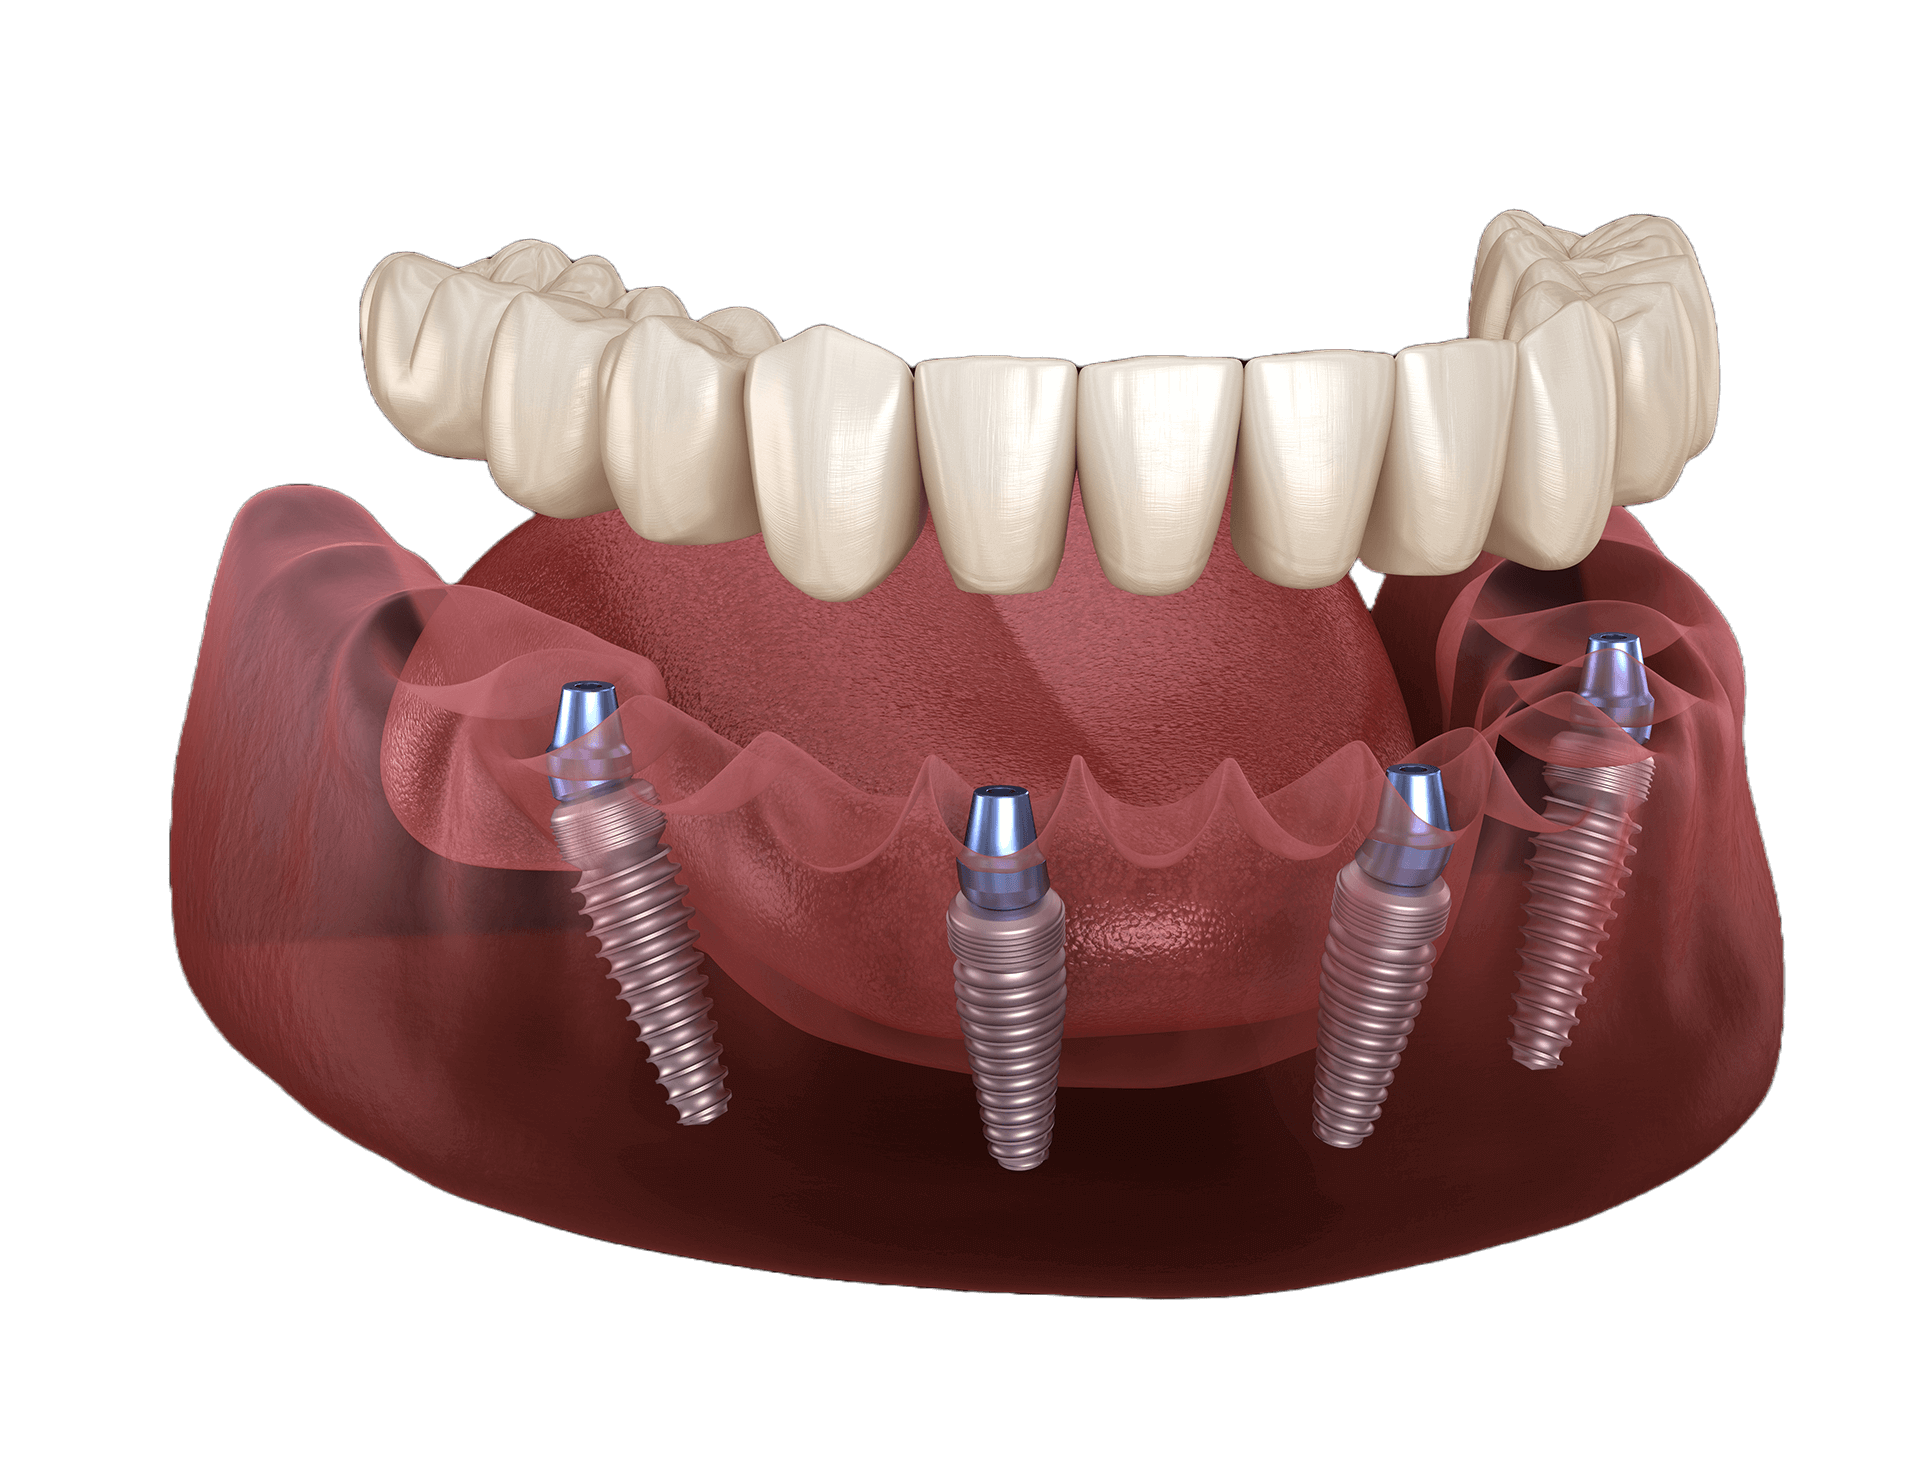

Implant dentures (also called implant-retained dentures or snap-in dentures) are removable teeth that attach securely to two to four dental implants placed in your jaw. These implants provide a strong, stable foundation that lets you eat, speak, and smile with confidence.

Unlike traditional dentures that rest on your gums and may slip or require adhesives, implant dentures lock onto titanium posts placed in your jawbone. This added stability helps prevent slipping and gives you a more natural feel.

How Do Snap-In Dentures Work?

- We place 2–4 dental implants in your jawbone during a minor surgical procedure.

- Implants are fitted with connectors called locators or attachments.

- Your custom denture is made to snap securely onto these connectors.

WHY ALL-ON-4 IMPLANTS?

- Denture Permanently Fixed With Implants

- New teeth in as little as one day

- Minimally invasive procedure